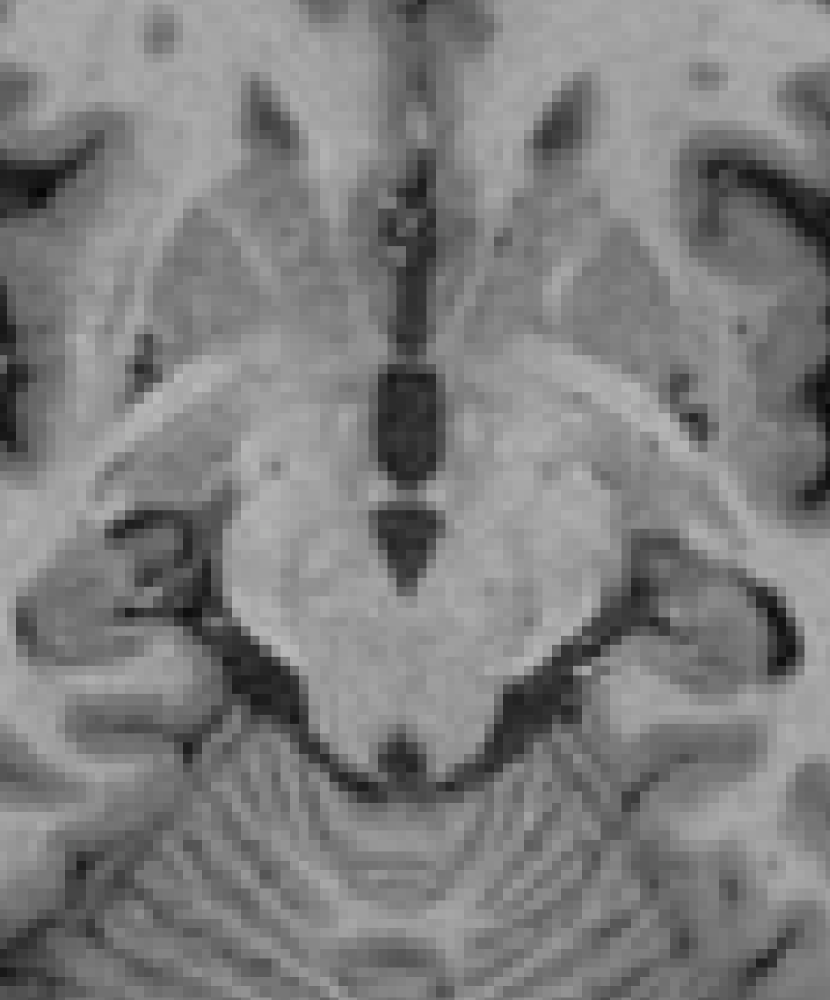

3.4 Post-processing

Contrast-driven post-processing techniques may lead to unexpected/unsatisfactory smoothing results. For instance, sub-cortical structures and some parts of the brainstem could be shrunk in this step due to low contrast with surrounding areas as shown in Fig. 7. However, this does not signify that the method is not capable of refining the segmentation since both the intensity features and the prior probabilities take part in the process.

Refer to caption

(a)

(b)

(c)

(d)

Figure 7: Two input slices in which low contrast between the region of interest and the surrounding areas is exhibited. In the image (a) the focus is on the mesencephalon which is highlighted by the purple area in (b). In (c) the focus is on caudate, putamen, pallidum and thalamus structures presented in green in (d).